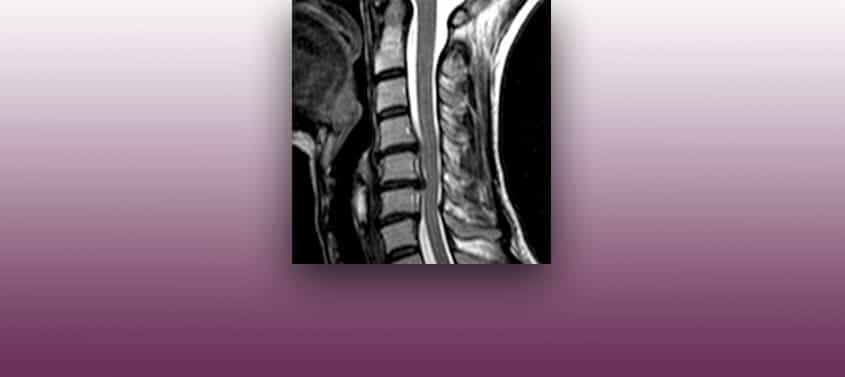

كما هو الحال في فتق الأقراص الصدرية، فإن فتق القرص الفقري العنقي يمكنه التأثير على الجذور العصبية أو على الحبل الشوكي العنقي، و عند هذا المستوى لديه مساحة أكبر من تلك التي في مستوى الظهر أمام الألم العنقي الذي يتمدد حتى يصل إلى الذراعين، يرافقه وخز في اليدين و أحيانا فقدان القوة و تنمل في القدمين، […]